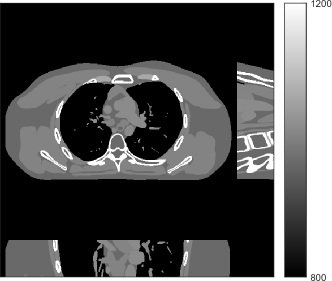

We simulated 3D axial cone-beam scans using a XCAT phantom with mm and mm. We generated sinograms of size using GE LightSpeed cone-beam geometry corresponding to a mono-energetic source with , , , and incident photons per ray and no scatter, respectively. Tab. I shows percentages of non-positive measurements under different dose levels. We set these non-positive measurements to for generating the post-log sinogram that PWLS-based methods rely on [13]. We reconstructed the 3D volume with a size of at a coarser resolution of mm and mm. The patch size during reconstruction was and the stride was . For evaluating reconstruction performance, we chose an ROI that was composed of the central 64 out of 96 axial slices, and refer to it as the reconstruction targeted ROI. Fig. 1 shows the central slices of the true XCAT phantom inside this ROI along three directions. In the reconstruction stage of PWLS-ULTRA and SPULTRA, we used 4 iterations for the image update step, i.e., , for a good trade-off between algorithms’ convergence and computational costs. We used ordered subsets, i.e., , to speed up the algorithm. The initial image for the ULTRA methods was reconstructed by PWLS-EP, whose regularization parameter was set empirically to ensure good reconstruction quality as for all the experimented dose cases. We used an analytical filtered back-projection (FBP) method FDK [59] to initialize PWLS-EP. The FDK images of XCAT phantom for all the dose levels are shown in the supplement. Due to the fact that SPULTRA has a similar cost function as PWLS-ULTRA in each outer iteration, we used the same parameter settings for both methods: and , which we observed worked well for all the dose levels we tested.